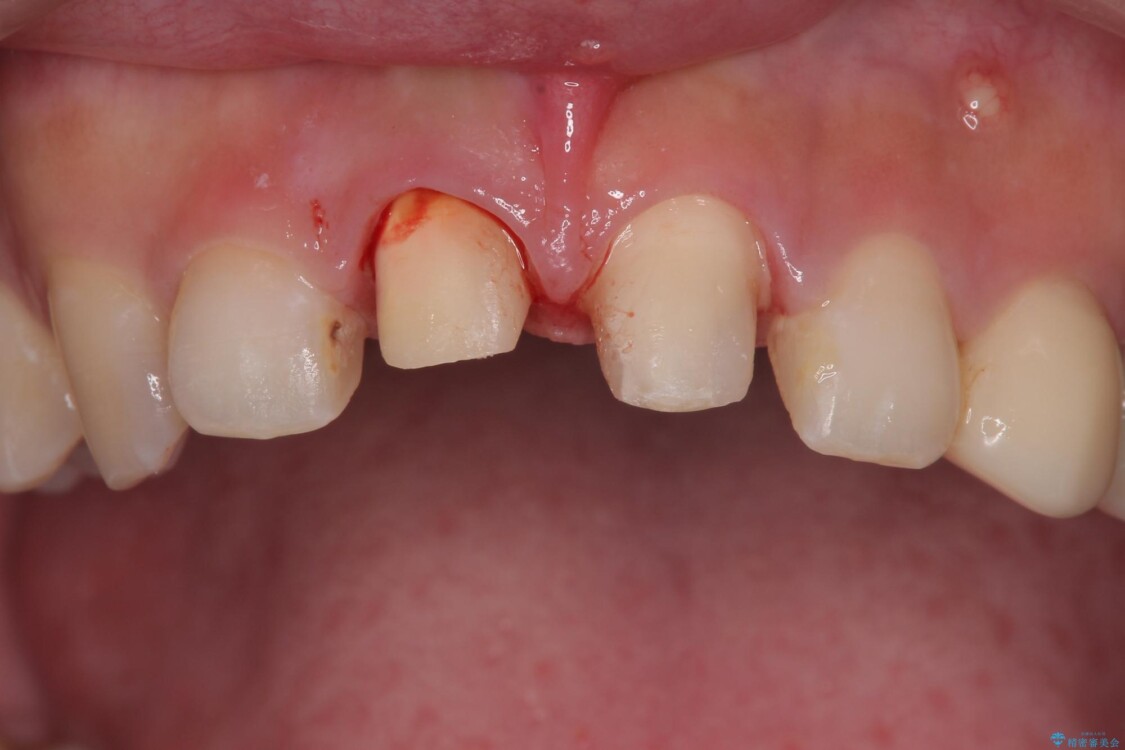

20代女性の患者様。 他院にて「上の前歯(右上中切歯)は抜歯してインプラントかブリッジにする必要がある」と診断され、大変ショックを受けられていました。 すでに根管治療を受けた歯でしたが、急に担当医が変わり、「抜歯が必要」とだけ説明されたことに不安感を抱き、当院を受診されました。 左上中切歯と犬歯も仮歯のままで、将来への不安が大きかったご様子です。

精密検査の結果、右上中切歯には**フェルール(歯の周囲の健全な歯質)**がほぼ存在せず、このままの状態での保存は困難と判断しました。

▶右上中切歯

抜歯後、即時インプラント埋入

審美性を考慮し、仮歯を即日装着

治療期間を最小限に抑えつつ、自然な前歯のラインと歯ぐきの形を維持

治療前

• 「抜歯してブリッジ」と言われた20代女性が選んだ治療とは|たった4か月で自然な笑顔に抜歯即時インプラント+審美補綴の症例 治療前画像